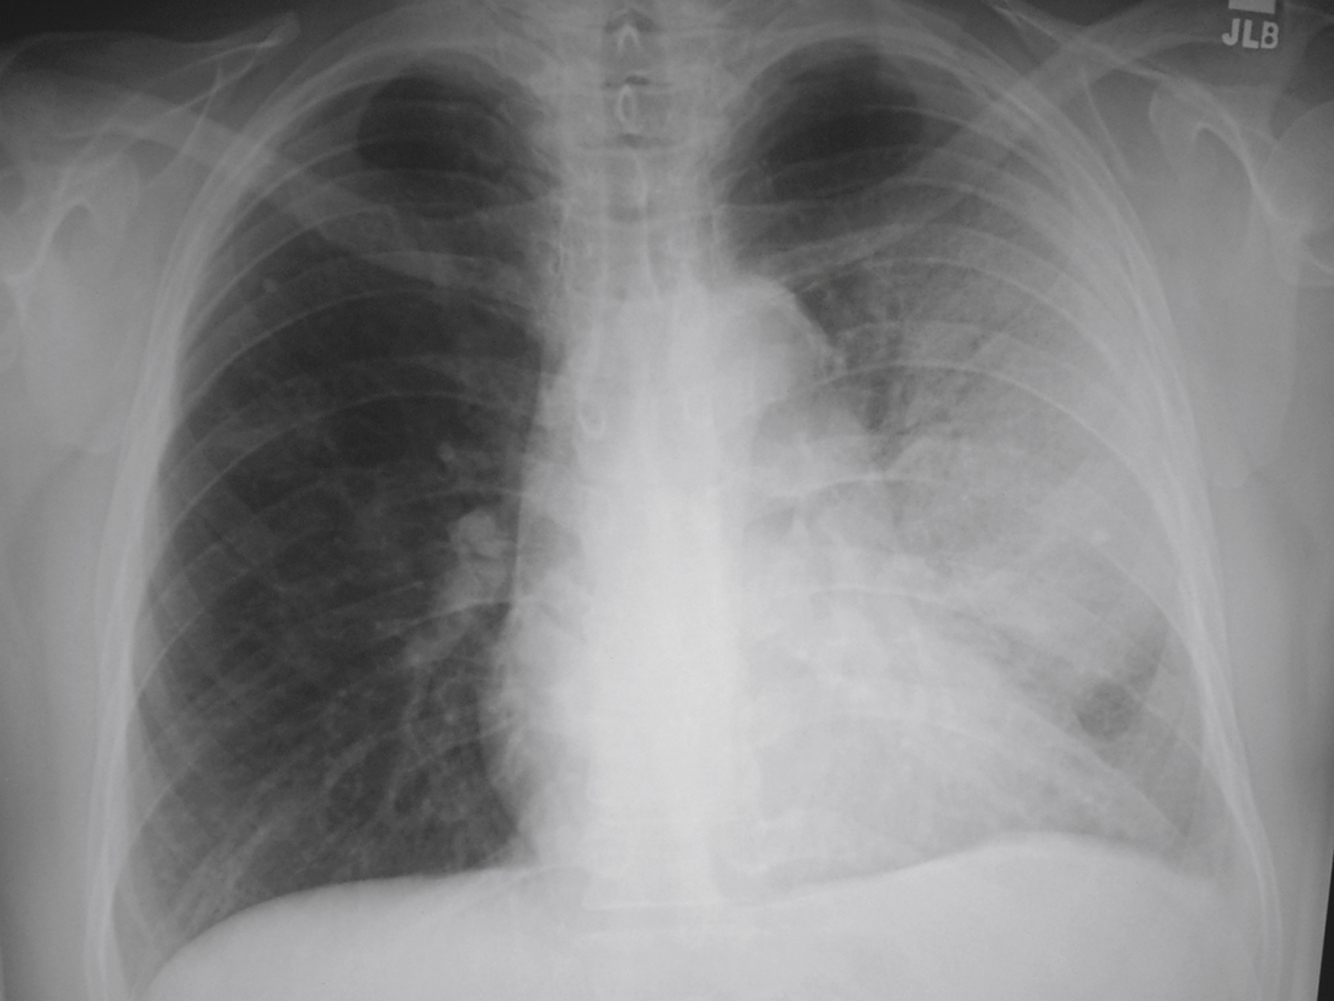

Q

List 1 bacterial PNA suggestive of this CXR

A

Mycoplasma

= pathcy interstitial infiltrates